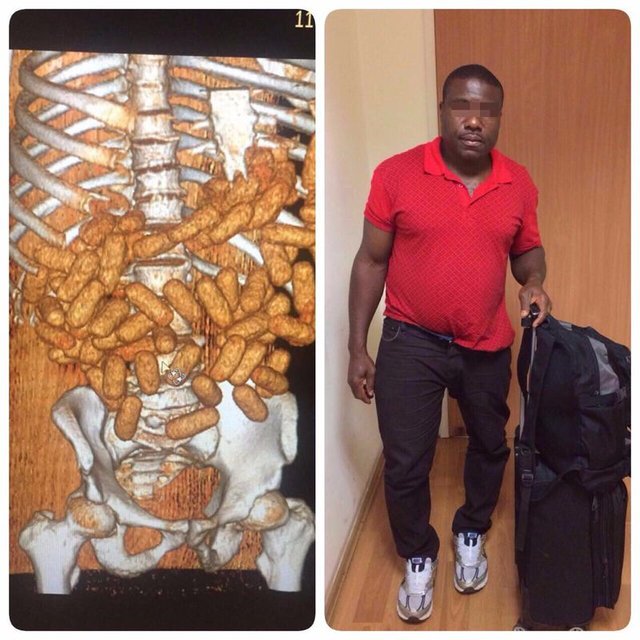

ORANTISIZ GÖBEKLE YAKAYI ELE VERDİ!

İstanbul Sabiha Gökçen Havalimanı’nda düzenlenen operasyonda, vücuduna sardığı 12 kilo 297 gram altınla yurda girmeye çalışan Gürcistan uyruklu Amınat Madagova gözaltına alındı. Gazete Habertürk'ten Nihat Uludağ'ın haberine göre yakalanan altının piyasa değerinin 2 milyon TL olduğu öğrenildi. İstanbul Gümrük Muhafaza Müdürlüğü ekipleri, Sabiha Gökçen Havalimanı’nda Tiflis’ten İstanbul’a gelen Gürcistan uyruklu Amınat Madagova isimli kadının göbek bölgesindeki orantısız büyüklükten şüphelendi.

Madagova, gümrük ekipleri tarafından detaylı arama yapılmak üzere gözaltına alındı. Yapılan üst aramasında, Madagova’nın vücuduna sardığı 12 kilo 297 gram altın ele geçirildi. Altının gümrüklenmiş piyasa değerinin 2 milyon TL olduğu ifade edildi.

‘RİCA ETTİLER’

Kaçak altınları Rusya’dan alarak Gürcistan’ın Tiflis kenti üzerinden İstanbul’a getirdiğini söyleyen Madagova, “Altınlar kız kardeşimin bir arkadaşına ait. Benden rica ettiler. ben de altınları taşıdım” dedi. Gürcistan uyruklu Amınat Madagova hakkında altın kaçakçılığı suçlamasıyla adli işlem başlatıldı.

HEPSİ SİNDİRİM SİSTEMİNDEN ÇIKTI

Etiyopya'dan İstanbul'a gelen uçaktaki Nijeryalı bir yolcunun vücuduyla orantısız büyüklükteki göbeğinden şüphelenen polisler yolcuyu durdurdu. Kontroller sırasında Nijeryalı C.K.O.'nun midesinde 85 kapsüldeki toplam 2 kilogram kokain bulundu. Kapsüller ilaç yardımıyla çıkarılırken, şüpheli tutukladı.

Habertürk Haber Merkezi'nden Yusuf Doğan'ın haberine göre İstanbul Narkotik Suçlarla Mücadele Şube Müdürlüğü ekipleri, 11 Eylül 2017 günü Etiyopya'nın başkenti Adis Ababa'dan İstanbul'a gelen uçaktaki bir yolcunun vücuduna göre orantısız şişkin olan göbeğinden şüphelendi.